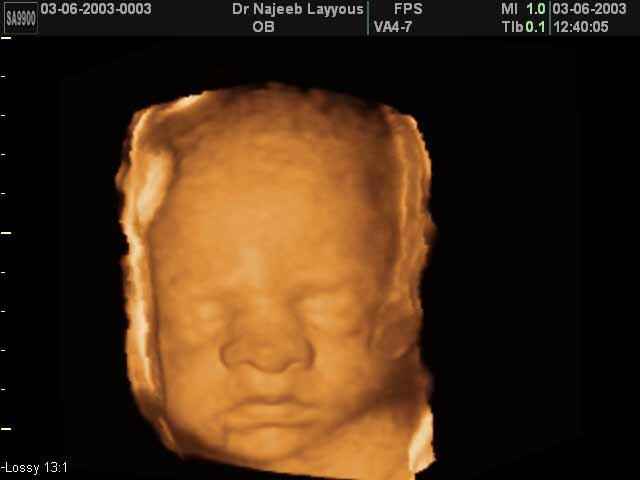

- Fetal Face Ultrasound Photos

3D Fetal Face Ultrasound Scan Photos | Dr N Layyous